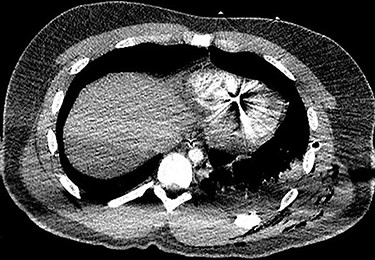

A 25-year-old male presented to the emergency department with four gunshot wounds to the right hip, right flank, left flank and left posterior thorax. Upon arrival the patient was hemodynamically stable with a Glasgow coma score of 15. Chest and abdominal plain films demonstrated a left-sided hemothorax, scattered bullet fragments within the left hemithorax and multiple bullet fragments in the abdominal cavity. A left tube thoracostomy was placed yielding immediate output of 575cc sanguineous fluid and the patient was taken for an exploratory laparotomy. A left diaphragmatic defect was identified with splenic herniation into the left thorax. Splenectomy and primary diaphragmatic repair were performed. Multiple bowel injuries were encountered necessitating several segmental resections. The next day a computed tomography (CT) scan of the chest, abdomen and pelvis was obtained, which identified presence of two bullet fragments in the interventricular septum (Figs 1 and 2).

Axial CT scan of the chest identifying bullet fragment in the interventricular septum.